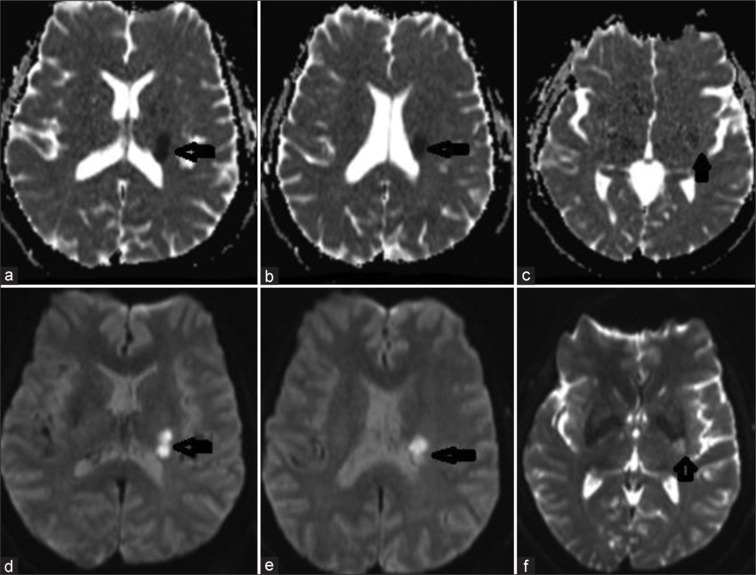

囊膜预警综合征(CWS)是一种罕见的疾病,其特征是复发性、典型的短暂性脑缺血发作(tia),影响面部、手臂和腿部,没有皮层受累。它与7天内发生全面中风的高风险有关。确切的病理生理机制和最佳管理策略仍有争议。区分CWS和渐强性tia至关重要,如果在全身再灌注治疗窗口内出现新的发作,则考虑再灌注治疗,以防止致残性卒中。我们报告一例53岁男性患者,因右偏瘫和面部虚弱持续1小时来到急诊科(ED)。在过去的7小时内,他经历了四次复发,典型发作,并被诊断为TIA,尽管在溶栓治疗窗口内。他开始双重抗血小板治疗,大剂量他汀类药物,并管理其他血管危险因素。然而,在24小时内,他的病情发展为完全中风,伴有严重的偏瘫和面部无力。磁共振成像证实左半球梗死,而计算机断层扫描血管造影正常。该病例强调了在ED中及时识别CWS的重要性,使卒中服务得以启动,并在适当时考虑再灌注治疗,以尽量减少致残性卒中的风险。

Capsular warning syndrome (CWS) is a rare condition marked by recurrent, stereotypical transient ischemic attacks (TIAs) affecting the face, arm, and leg, without cortical involvement. It is associated with a high risk of a full-blown stroke within 7 days. The exact pathophysiological mechanism and optimal management strategies remain debated. It is crucial to distinguish CWS from crescendo TIAs and consider reperfusion therapy if new episodes occur within the therapeutic window for systemic reperfusion, in order to prevent a disabling stroke. We present the case of a 53-year-old male who arrived at the emergency department (ED) with right hemiparesis and facial weakness lasting for 1 h. He had experienced four recurrent, stereotypical episodes over the past 7 h and was diagnosed with a TIA, despite being within the therapeutic window for thrombolysis. He was started on dual antiplatelet therapy, high-dose statins, and management of other vascular risk factors. However, within 24 h, his condition progressed to a complete stroke with severe hemiparesis and facial weakness. Magnetic resonance imaging confirmed infarction in the left hemisphere, while a computed tomography angiogram was normal. This case underscores the importance of prompt recognition of CWS in the ED, enabling activation of stroke services and the consideration of reperfusion therapy when appropriate, to minimize the risk of a disabling stroke.